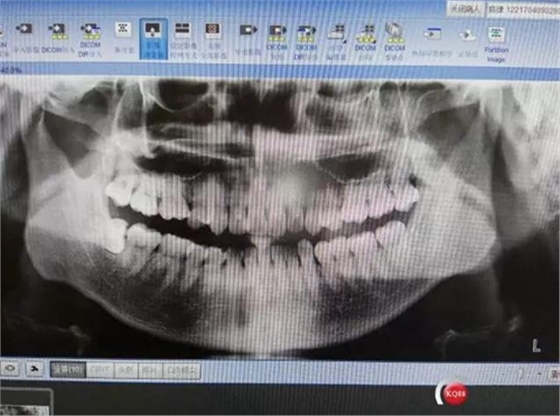

曲面斷層片結(jié)果回示:

48水平向阻生,根尖影像與下牙槽管重疊。

診斷:48完全水平向阻生,牙周結(jié)石二度